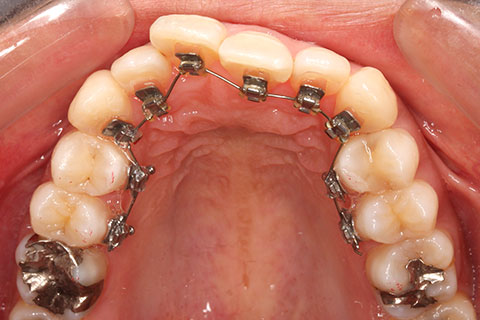

ハーフリンガル矯正3:上の歯のみ舌側矯正で治療(矯正期間24ヶ月)

治療前

治療中(開始直後)

治療中(開始半年後)

治療後

- 年齢・性別

- 25歳女性

- 治療期間

- 2年0ヶ月

- 抜歯

- 上下4番抜歯

- 治療費

- 110万円

- 治療内容

- 施術の副作用(リスク)

- 表側矯正と比較して、力学的な操作性が複雑なため、ボーイングエフェクトを起こしやすい。